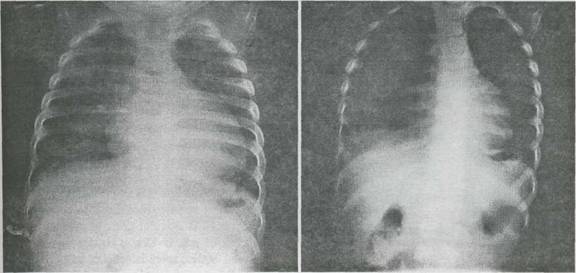

Fig. 9-16. Miocardita acuta virala la un sugar īn vārsta de 7 luni. Radiografie cardiopulmonara.

A. Cardiomegalie importanta cu hipertrofie ventriculara stānga.

B. Cord de dimensiuni normale dupa 16 saptamāni de tratament.